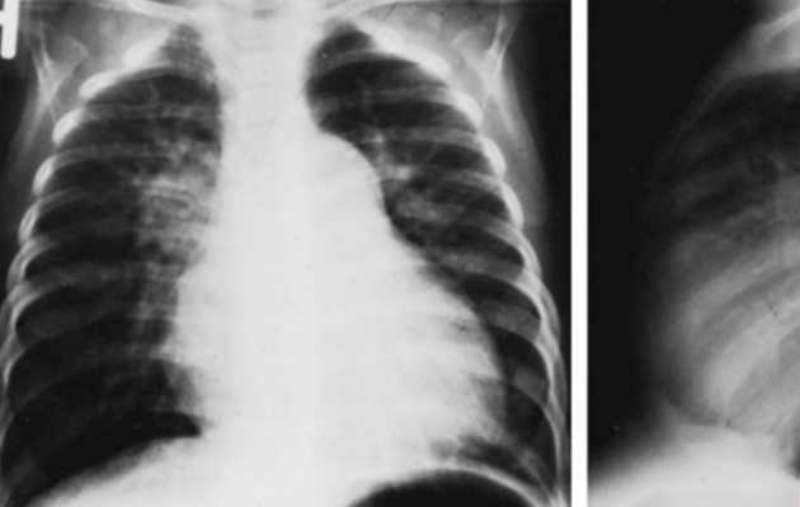

Lungenentzündung, fachlich Pneumonie genannt, ist eine schwere entzündliche Erkrankung, die die Lungen betrifft. Sie kann durch verschiedene Erreger verursacht werden, einschließlich Bakterien, Viren und in manchen Fällen auch durch atypische Mikroorganismen. Diese Erkrankung ist nicht nur eine Form von Infektion, sondern vielmehr ein komplexes Bündel von Erkrankungen, die sich auf unterschiedliche Weise äußern können. Welche Symptome können auf eine Lungenentzündung hinweisen und werden oft übersehen?

Anzeichen und Symptome einer Pneumonie

Eine Pneumonie kann sich auf unterschiedliche Weise äußern, abhängig vom Erreger und dem allgemeinen Zustand des Patienten. Zu den häufigsten Symptomen gehören: